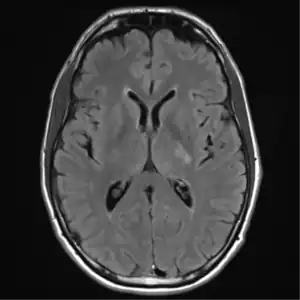

MRI brain: cryptococcus

The immune reconstitution inflammatory syndrome (IRIS) has been described in those with normal immune function with meningitis caused by C. gattii and C. grubii. Several weeks or even months into appropriate treatment, there can be deterioration with worsening meningitis symptoms and progression or development of new neurological symptoms. IRIS is however much more common in those with poor immune function (≈25% vs. ≈8%).Magnetic resonance imaging shows increase in the size of brain lesions, and CSF abnormalities (white cell count, protein, glucose) increase. Radiographic appearance of cryptococcal IRIS brain lesions can mimic that of toxoplasmosis with ring enhancing lesions on head computed tomography (CT). CSF culture is sterile, and there is no increase in CSF cryptococcal antigen titre.